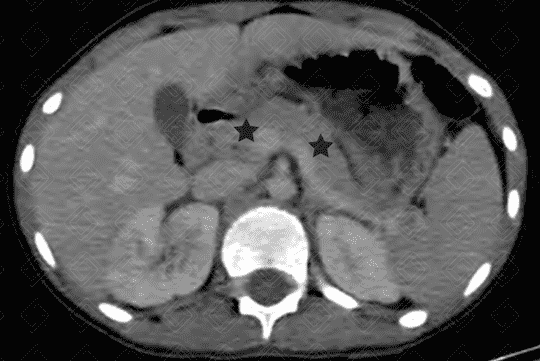

• Tomografia computadorizada do abdome com contraste venoso, evidenciando pâncreas com espessura e densidade normais (asteriscos pretos);

• Pâncreas normal (figura 1);